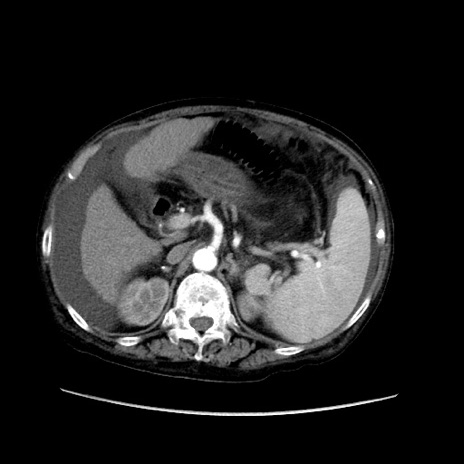

冠状断像

【症例】80歳代 女性

【主訴】腹部膨満感

【現病歴】他院にて肝硬変にてフォロー中。1週間前から便秘、腹部膨満感、臍部腫瘤あり受診となる。

【既往歴】肝硬変

【身体所見】腹部膨隆あり、皮膚変化なし、疼痛なし。

【データ】WBC 4600、CRP 0.25